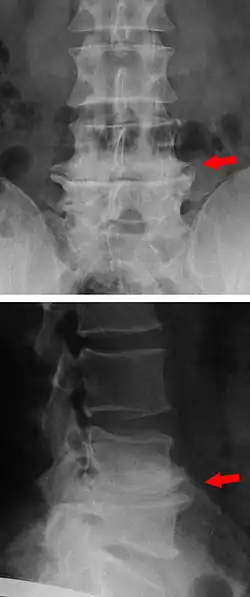

Die Formveränderung der Wirbelkörper im Sinne der Spondylophyten (Spondylose) und die Minderung des Zwischenwirbelraums durch Höhenverlust der Bandscheiben sind im konventionellen Röntgenbild gut sichtbar. Auch der Verschleiß der Wirbelbogengelenke (Spondylarthrose) zeigt sich hier deutlich.